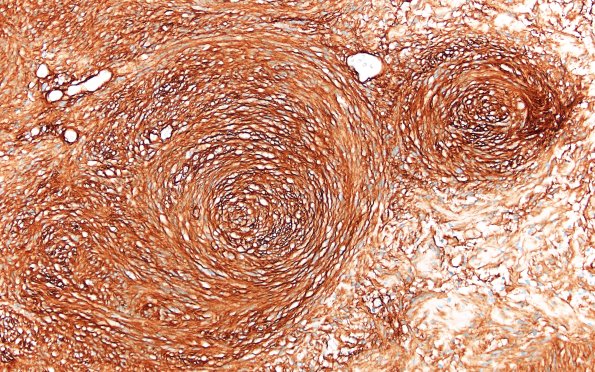

Washington University Experience | NEOPLASMS - CRANIAL AND PARASPINAL NERVEs | Schwannoma | 31D3 Schwannoma, whorled NF2 (Case 31) CollIV 20X

3 The basement membrane of this tumor is strongly stained for collagen IV. (Coll IV IHC)